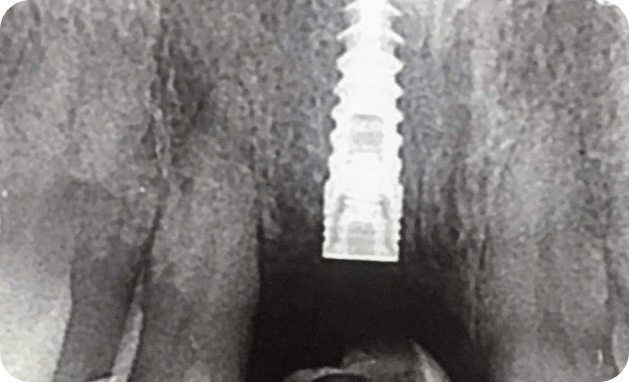

Casos

Instalaciones oral group Instalaciones oral group Instalaciones oral group Instalaciones oral group Instalaciones oral group Instalaciones oral group Instalaciones oral group